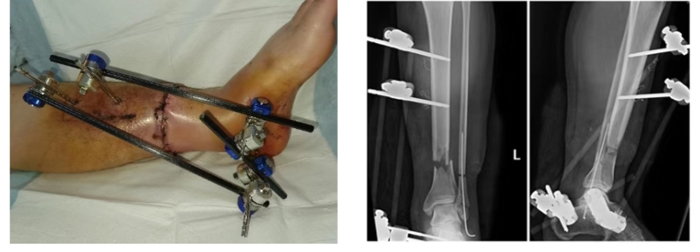

經(jīng)過(guò)積極的術(shù)前準(zhǔn)備,手術(shù)順利進(jìn)行。在術(shù)前預(yù)訂方案指導(dǎo)下,依次對(duì)創(chuàng)面進(jìn)行徹底清創(chuàng)、骨折復(fù)位外固定,吻合動(dòng)靜脈血管(6支)、縫合神經(jīng)、肌腱,關(guān)閉傷口。當(dāng)?shù)谝粭l脛后動(dòng)脈血管吻合后離斷的肢體迅速恢復(fù)了血運(yùn)。手術(shù)由潘維亮主任醫(yī)師、張亞州主治醫(yī)師、段修芳主治醫(yī)師、張俊國(guó)主治醫(yī)師共同參與、交替操作完成。凌晨4:50患者離斷肢體血循環(huán)系統(tǒng)建立通暢,再植手術(shù)順利完成。整個(gè)手術(shù)過(guò)程歷時(shí)7小時(shí)余。術(shù)后遠(yuǎn)端肢體血管充盈良好,顏色紅潤(rùn)、皮溫正常。鑒于手術(shù)時(shí)間長(zhǎng),遂轉(zhuǎn)入ICU行生命體征監(jiān)護(hù)。

手術(shù)1周后,再植肢體度過(guò)了術(shù)后發(fā)生血管危象的可能。目前再植肢體完全存活,其他功能也在逐步恢復(fù)中。潘維亮主任認(rèn)為患者風(fēng)險(xiǎn)期還沒(méi)有完全度過(guò),需繼續(xù)密切觀察。